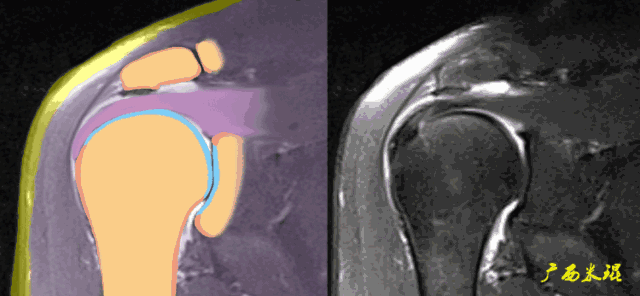

2、斜矢状位:垂直于冈上肌长轴,观察肩峰形态及喙肩弓,观察肩袖4个组分的短轴断面。